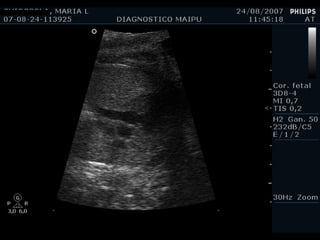

Evaluación del corazón fetal en la ecografía obstétrica Modo B ¿CUANDO? Segundo y tercer trimestres ¿Como? De mayor a menor

1) LONGITUDINAL / CEFALICA / DORSO IZQ

Apex y estómago: ¿Cerca o lejos del transductor? Lejos Long/Cef/D.izq